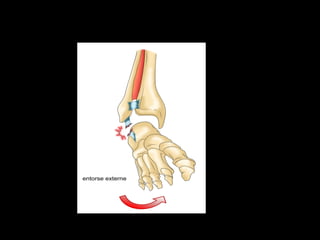

2. ARTHROLOGIE

• Une articulation est la jonction entre deux os.

• Les tissus conjonctifs, ligaments, relient les os